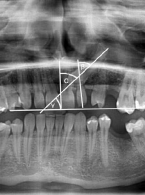

Resorpcja korzeni zębów sąsiadujących z zatrzymanym kłem – przegląd piśmiennictwa. Część I

Resorption of the roots of teeth adjacent to the retained canine – review of the literature. Part I

Ewa Imiełowska, Agnieszka Richter, Małgorzata Świstek